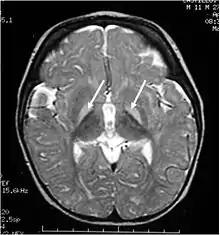

Unbound plasma bilirubin past a threshold exerts neurotoxic effects through triggering diversified metabolic cascades. It decreases oxygen consumption and increases neuronal apoptosis directly or indirectly through release of pro-inflammatory enzymes by glial cells.[32] Primary targets affected are the basal ganglia, brainstem and cerebellum due to differential tissue binding, bilirubin uptake and cell's higher sensitivity to injury.[32][33]

As this damage is irreversible, prophylactic treatment is essential to avoid critically high bilirubin levels.